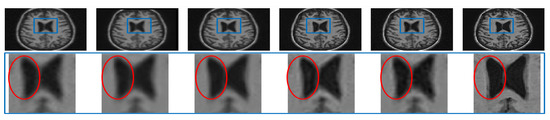

The performance of the proposed single framework for the super resolution of noisy MR images has been evaluated here for 2% Gaussian noise and different upsampling factors. For existing SR methods, the images are first denoised using AONLM [40]. The qualitative results using different algorithms for upsampling a randomly selected noisy image by factor 2 are shown in Figure 13. To illustrate the significance of the proposed approach for efficient denoising as well as the preservation of image details, different kinds of regions are zoomed and shown separately. The green box in Figure 13 comprises the region with strong edges, the red box shows the region with minor edges and texture, and the cyan box shows the smooth region. It can be observed that the reconstructed image using spline interpolation and the non local means in three dimensions (NLM3D) approach in Figure 13b,c blur the image details in every kind of region and hence provide poorer contrast but with better denoising in each region. The LRTV method, however, tends to provide better contrast among tissues and preservation of image details, yet it is not able to provide efficiently denoised smooth regions (see red and cyan boxes in Figure 13d). The proposed work, on the contrary, can be observed to reconstruct strong edges while preserving the image details with limited noise (see green box Figure 13e), it can relatively better suppress the noise in patches with smooth and texture/minor edges as compared to LRTV [12] (can be seen in red and cyan boxes), and it can provide improved contrast as compared to NLM3D [13]. It demonstrates that the proposed method tends to improve the trade-off between the preservation of image details and suppression of noise. The obtained PSNR, SSIM, and FSIM values for different subjects are summarized in Table 3 and show that the proposed work performs relatively better than existing unsupervised methods when combined with supervised denoising method.

Figure 13.

Demonstration of reconstruction quality of different kinds of regions/patches, region with edges (green boxes), region with texture (red boxes), and smooth region (cyan boxes), after super resolving real MR images degraded with downsampling factor 2 and 2% noise, using different algorithms. (a) NN interpolation of noisy LR image, (b) spline interpolation of denoised LR image, (c) NLM3D [13] applied on denoised LR image, (d) LRTV [12] applied on denoised LR images, (e) the proposed work applied on a noisy LR image, and (f) the original noise-free HR image.